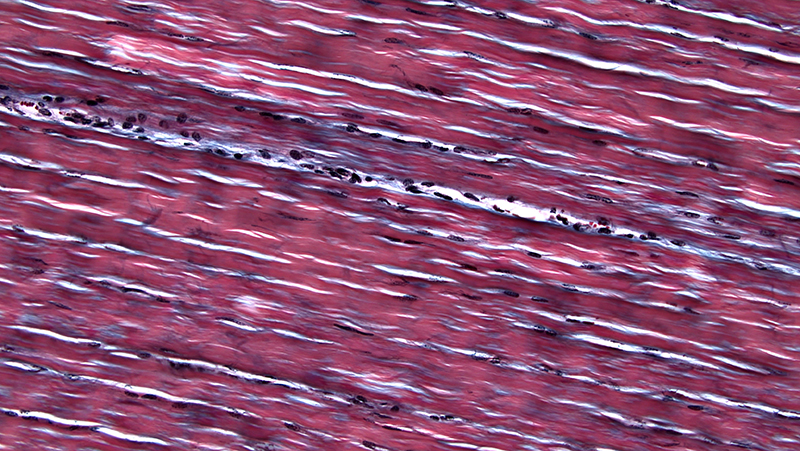

Elastic fiber

Note: All the pictures above are provided by Dr. Brian Matsumoto.